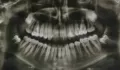

Верхняя челюсть и верхняя дуга зубного ряда.

Если речь идет о 21 зубе, то там однозначно периодонтит (хроническое воспаление).